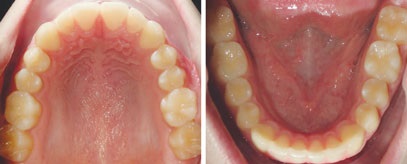

PATIENT INFORMATION:

• 14-year-old boy.

• Chief concern: overbite and crowding.

• Orthodontic diagnosis:

• Right side: Class II molar and canine (moderate).

• Left side: Class II molar and canine (severe).

• Overbite: severe deep bite.

• Upper arch: moderate crowding, with retroclined incisors.

• Lower arch: moderate crowding.

Figs. 3a-g: Initial records.